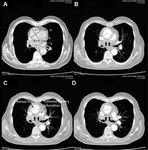

CT of a 71-year-old man showing type II dissecting aneurysm of the ascending aorta. Hematoma around the proximal segment of the ascending aorta (panels A-D) compressed the right pulmonary artery, almost occluding its patency and limiting the perfusion of the reciprocal lung

Stougiannos PN, Mytas DZ, Pyrgakis VN. The changing faces of aortic dissection: an unusual presentation mimicking pulmonary embolism. BMJ Case Reports 2009; doi:10.1136/bcr.2006.104414